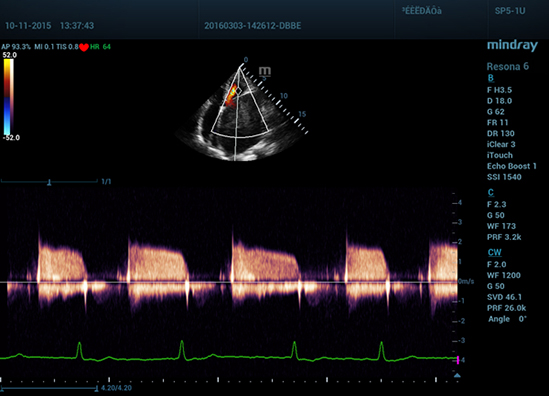

• Монокристальный секторный фазированный датчик, SP5-1U (1.5 - 4.5 МГц, 23.4 мм, 80 элементов)

Клинические изображения Mindray Resona 6: